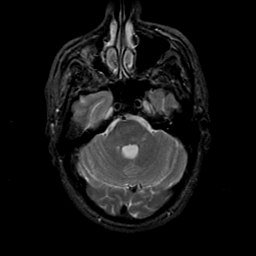

MR Study #21, November 3, 1991 -- Slice #13

[Home][Help][Clinical][Tour 1][Tour 2] Slice 13